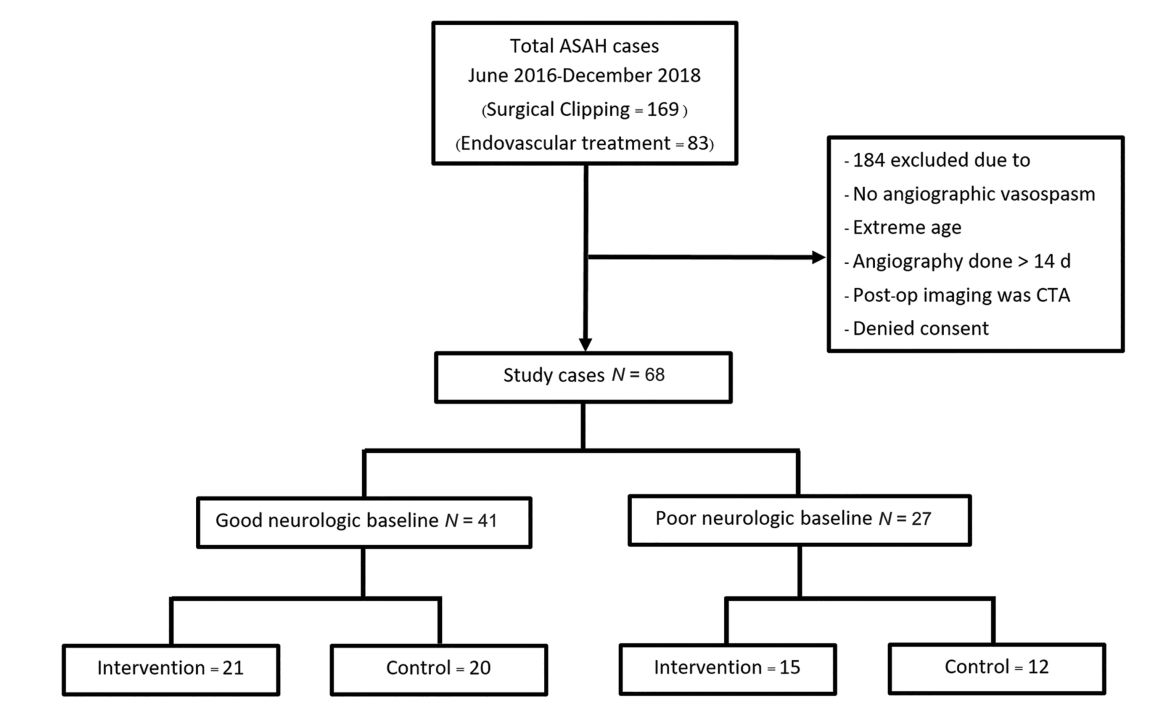

图1:纳入和排除患者流程图。